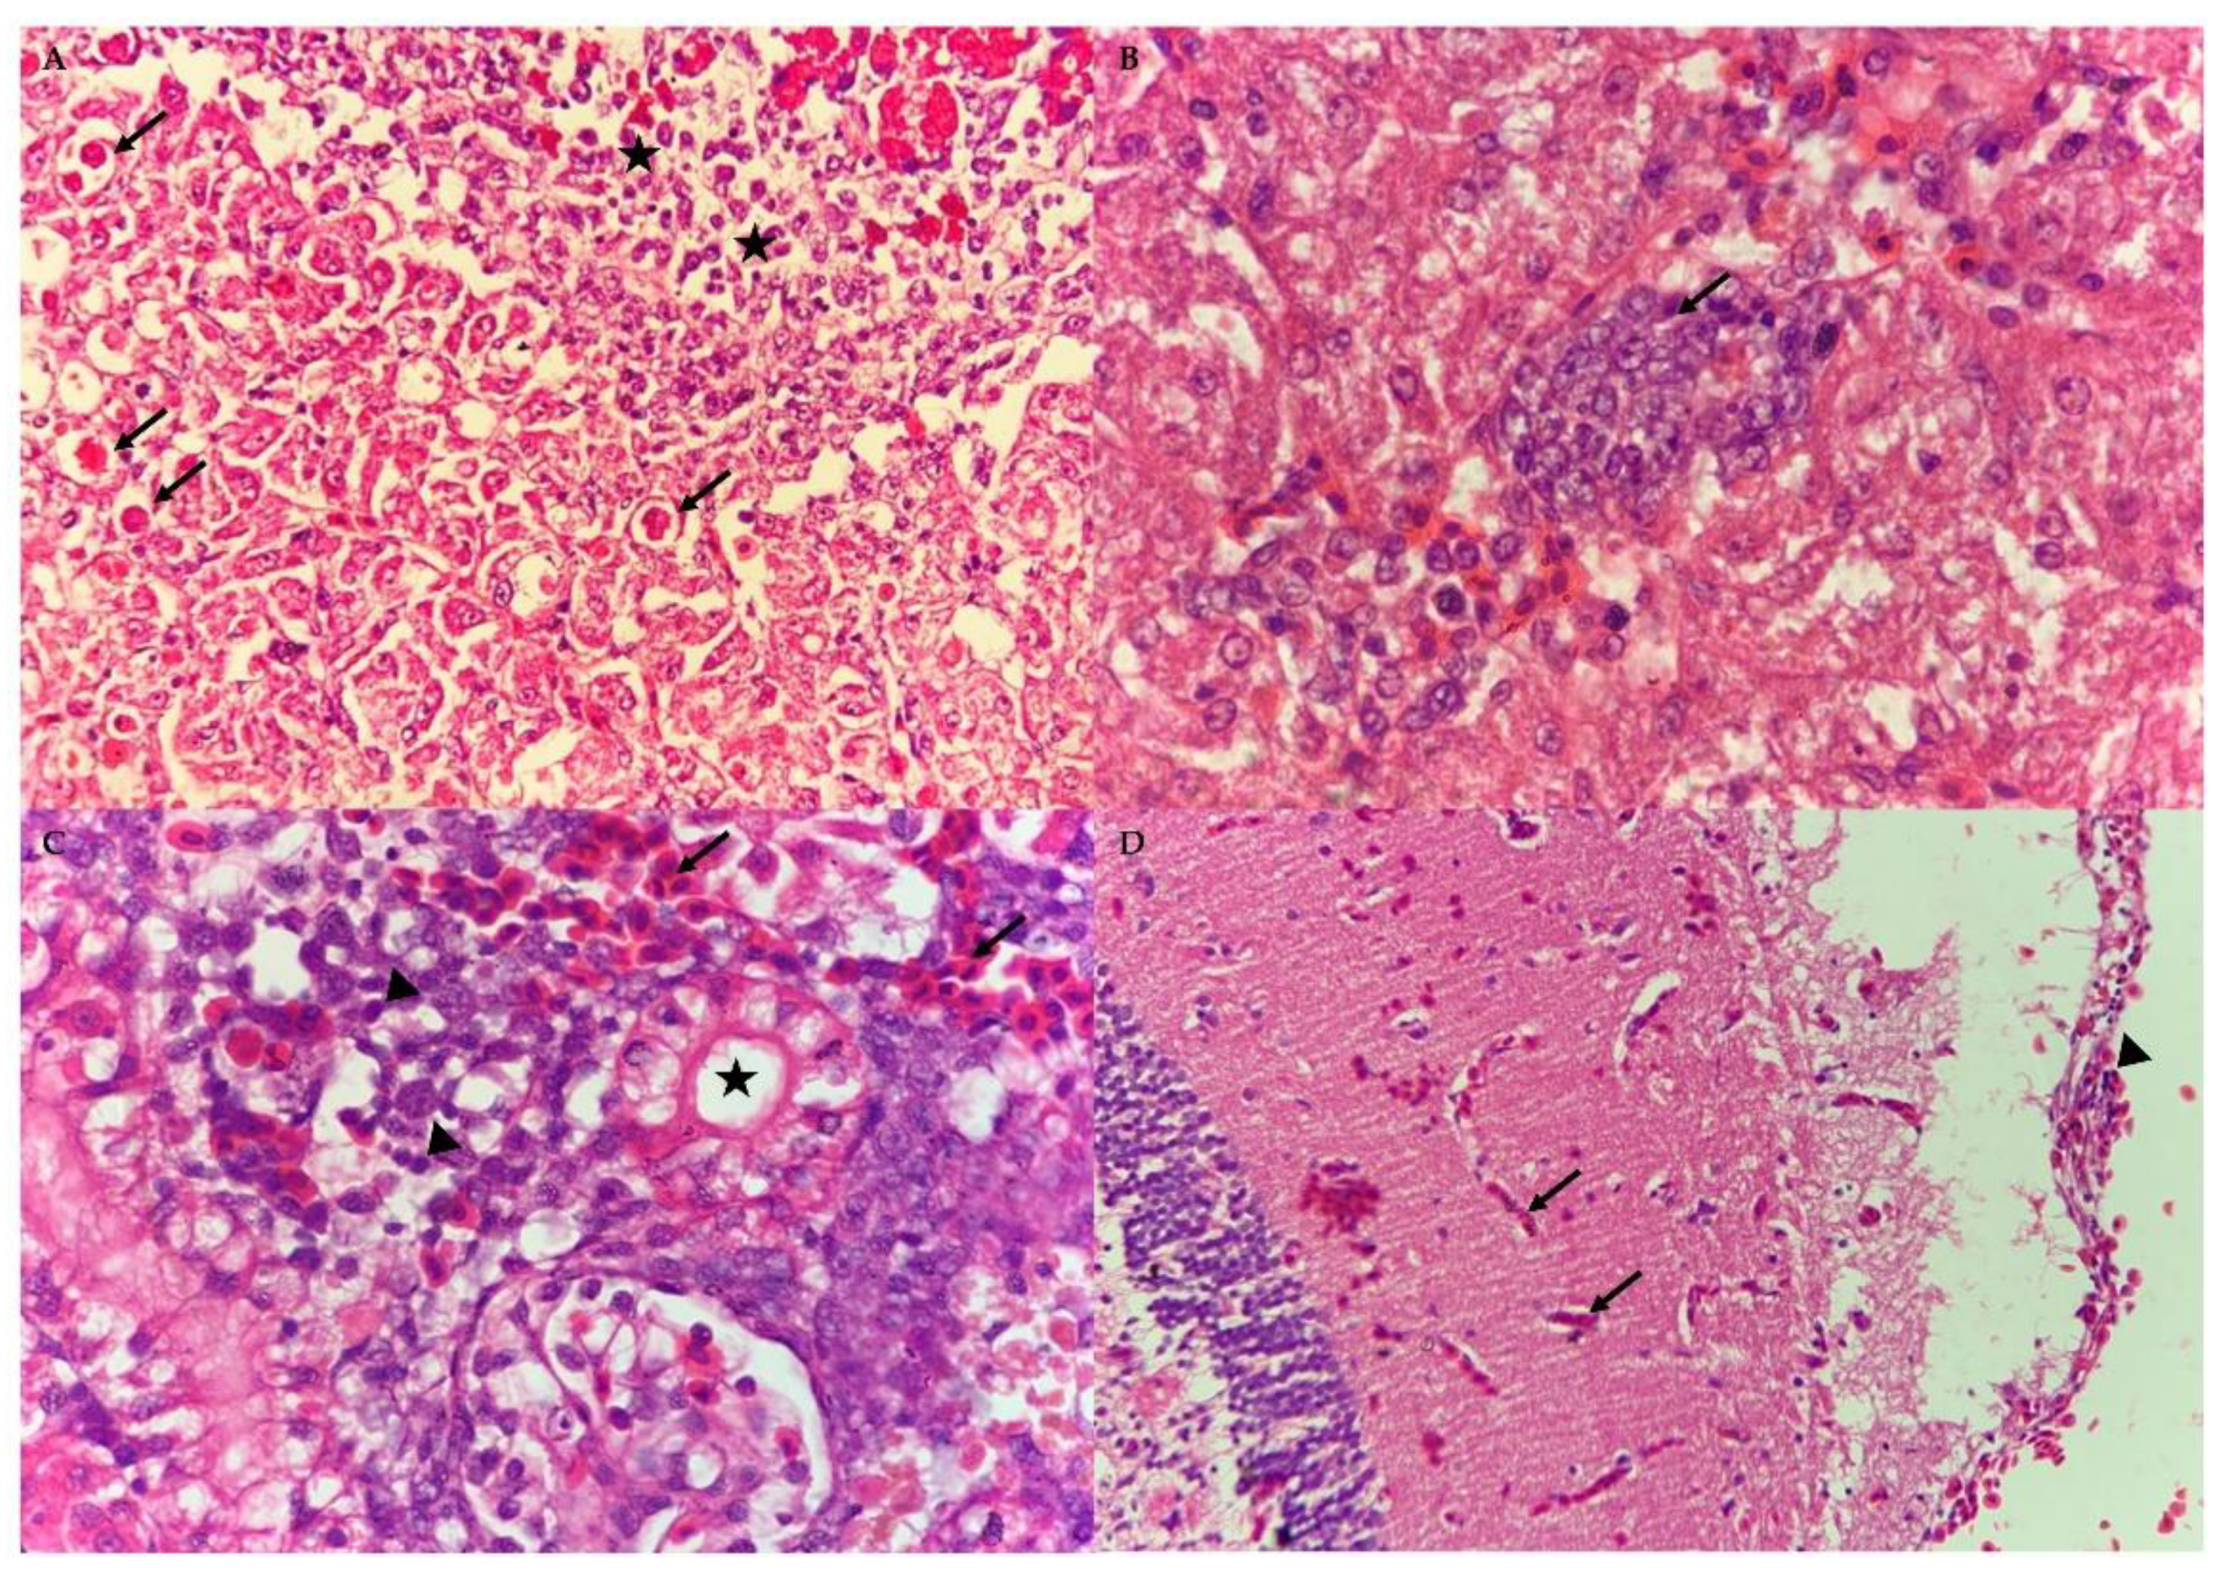

3.4. Histopathological Assessment